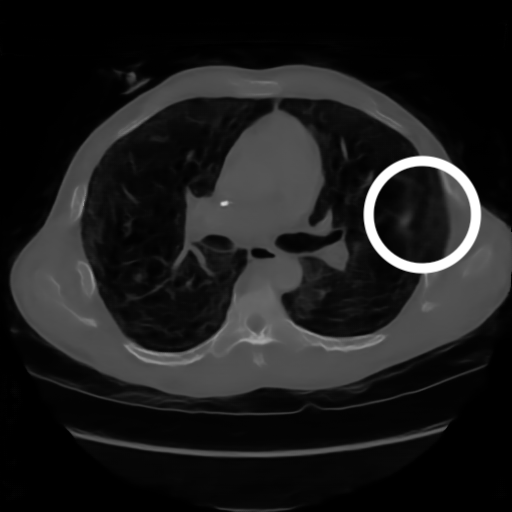

3.1.3 Example 2: data driven reconstruction methods in lung CT screening

There is sufficient evidence that screening for certain tumours using CT images may improve prognosis of cancer survivability (citep \@BBN(Boiselle, 2013)). As mentioned above, in order to gain better image quality with less X-ray dose, many enhanced regularization techniques with integrated machine learning steps have been suggested for CT reconstruction, and in a full reference setting they are commonly evaluated by applying PSNR and SSIM, see e.g. (citep \@BBN(Adler and Öktem, 2018; Hendriksen, Pelt, and Batenburg, 2020; Unal, Ertas, and Yildirim, 2021)). As CT images are generally taken to perform a clinical task, they are not the final step of a medical process but often the initial one. Therefore the definition of what makes a good image heavily depends on the task in hand, and for prognosis related cancer the identification of tumours is of upmost importance.

In on-going research on photon counting detector types and screening procedures for lung cancer (EPSCR grant: EP/W004445/1) an experiment was conducted testing enhanced reconstruction algorithms. Simulations using less than 10% of a clinical X-ray dose were performed to investigate if data-driven methods could sufficiently enhance the images to clearly see the tumours in the lungs while providing very low amount of dosage to the patients. The corresponding data was a CT-dose simulation, using images from the open LIDC-IDRI dataset (citep \@BBN(Armato et al., 2011)) as references, as well as simulated and reconstructed images with in-house software. Figure 3 shows the results of the experiment. We show the reference image used as basis for the simulation, together with five different reconstruction algorithms. The first is an iterative solver, a gradient descend algorithm with TV minimization (citep \@BBN(Sidky et al., 2012)) and (c)-(f) correspond to machine learning methods: FBPConvnet is a denoising algorithm that cleans the bad image (citep \@BBN(Jin et al., 2017)), LPD is an iterative unrolled method that combines traditional solvers with machine learning (citep \@BBN(Adler and Öktem, 2018)), Noise2Inverse is a self-supervised learning method (i.e. does not require ground truth data) (citep \@BBN(Hendriksen et al., 2020)) and ItNet is another iterative unrolled method, the best performing winner of the AAPM DL-Sparse-View CT challenge (citep \@BBN(Genzel, Macdonald, and März, 2021)). ItNet is also judged here as the best result according to PSNR, SSIM and LPIPS.

Figure 3: Reference image (a) and outputs of different reconstruction methods (b)-(f) applied to dose simulated data. PSNR/SSIM/LPIPS are unable to identify the best reconstruction (c), where also the tumour is visualized well.

FR-IQA mismatches

This experiment was performed to evaluate the quality of different kinds of CT reconstruction, and especially the lung tumour detection capabilities thereof. The best result according to the chosen IQA measures is given by ItNet in Figure 3(f), which performs visually poorly. Not only the tumour (zoomed in white circle) is significantly less visible in the reconstruction, but ItNet also produces structures in the lung that are different than the ones in the reference image; it blurs and lengthens much of the soft tissue present in the lungs and it also created structure from noise in some places. Moreover, the image is overly smooth. Comparing the other reconstruction algorithms, it seems that FBPConvnet Figure 3(c) is the one performing best at preserving the shape of the lung nodule, even when the resulting image contains enhanced pixel-level noise.

We can see here that the qualitative findings strongly contradict the numbers provided by the selected measures. The reconstruction of ItNet, Figure 3(f), is outperforming the other reconstructions in regards of the measures, and the qualitative winner FBPConvnet, Figure 3(c), is judged as second worst by the same measures. This experiment suggests that the discussed measures are not a good choice for that kind of CT reconstruction applications and are yielding misleading results.

While pixel-independent random noise may be a worse effect in a natural image than a slightly oversmooth reconstruction, this is not true in CT images, where small structures may disappear if smoothing is promoted against edge preservation. In iterative reconstruction algorithms such choices are explicitly made by choosing the prior appropriately, in data-driven models the researcher has limited control on the type of implicit priors the algorithm learns from the data, i.e. model builders do not know what the algorithms chooses to learn from the ground truth. In these cases appropriate evaluation would therefore be even more important to ensure quality. If this is followed by a blind evaluation using non-appropriate metrics, the promotion of less desirable images can happen, chosen by an implicit assumption on the metric rather than the actual goal of the task.